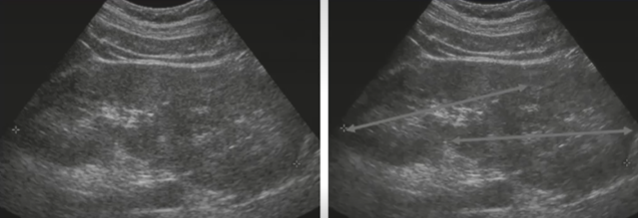

What grade of hydronephrosis is this?

splaying of the calyces—distinguish from peripelvic cyst by

imaging in two planes and showing communication with the ureter. Use

color Doppler to distinguish from renal vessels.

Grade 1

Fluid extends into major and minor calyces. "Bear Claw" or

"Cauliflower" effect.

Grade 2

Severe dilatation of the renal pelvis with loss of renal

parenchyma

Grade 3